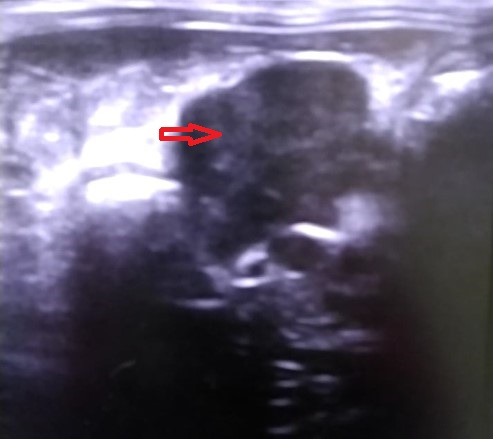

На УЗИ выявлено увеличение лимфатического узла в проекции подвздошной кишки-контуры не ровные, без изменения структуры, со снижением эхогенности (Рис. 1 и Рис 2.). Локальный оментит, илеит со снижением перестальтики, дифузное изменение паренхимы печени. Важно, что другие лимфоузлы и селезенка были без изменений.

Рис. 1 Изменённый лимфатический узел-красная стрелка.